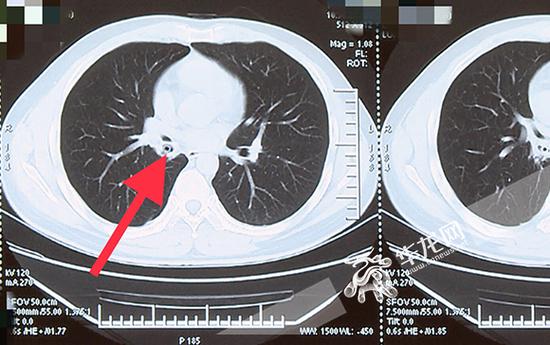

红箭头指示ct检查显示姚先生肺内的异物与常见的结核,肿瘤影像显示不